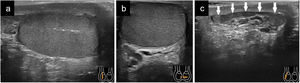

Quistes testicularesLos quistes simples aparecen aproximadamente entre un 8-10% de los pacientes y se asocian comúnmente a traumatismos, cirugía e inflamación. En la ecografía se distinguen anecogénicos, sin vascularización interna y con refuerzo acústico posterior, presentando tamaños variables (fig. 3a)7–9.

Ectasia tubular de la rete testisLa ectasia tubular de la red testicular es una entidad clínica benigna en la que la dilatación quística de la red testicular es el resultado de la obstrucción parcial o completa de los conductos eferentes, siendo un hallazgo frecuente en pacientes mayores de 50 años asintomáticos. En la ecografía se observa como múltiples estructuras anecogénicas, sin tejido blando ni vascularización Doppler, dentro del mediastino, siendo un hallazgo bilateral habitualmente (fig. 3a). La importancia radica en hacer un diagnóstico diferencial adecuado con lesiones malignas quísticas7–10.

Los quistes epididimarios se presentan en cualquier punto del epidídimo y suelen medir menos de 2cm (fig. 3b) y los espematoceles los encontramos en la cabeza y son mayores de 2cm. Los de mayor tamaño desplazarán el testículo, y los diferenciaremos del hidrocele, porque este último rodea al testículo.

Ecográficamente se caracteriza por aumento de flujo en el Doppler color. Suele ser unilateral. El epidídimo puede estar aumentado de tamaño y ser heterogéneo (vídeo 3). Puede existir hidrocele reactivo y engrosamiento de las cubiertas escrotales. Habitualmente comienza afectando a la cola del epidídimo y se extiende al cuerpo y a la cabeza y si la infección progresa también al testículo (orquioepididimitis). En la orquitis el testículo puede presentar una ecogenicidad heterogénea y hay un aumento del flujo en el Doppler-color en el testículo afecto, al compararlo con el contralateral1,14,28,29 (Fig. 7).

a) Epididimitis con engrosamiento e hipoecogenicidad del epidídimo (señalado con flechas y medido su grosor entre cruces); b) Orquitis avanzada con zonas de marcada hipoecogenicidad del parénquima testicular y área periférica abscesificada con captación Doppler; c) Evolución de «b» una semana después con área abscesificada en polo inferior testicular con hidrocele tabicado secundario (señalado con flechas).